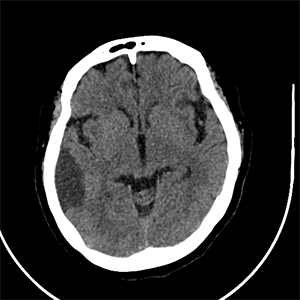

#AJNRcc >> October 30, 2025 >> What is the diagnosis for this 46-year-old man with seizures for more than 2 months. Submit your answer at https://t.co/FSqHPsLbMs.